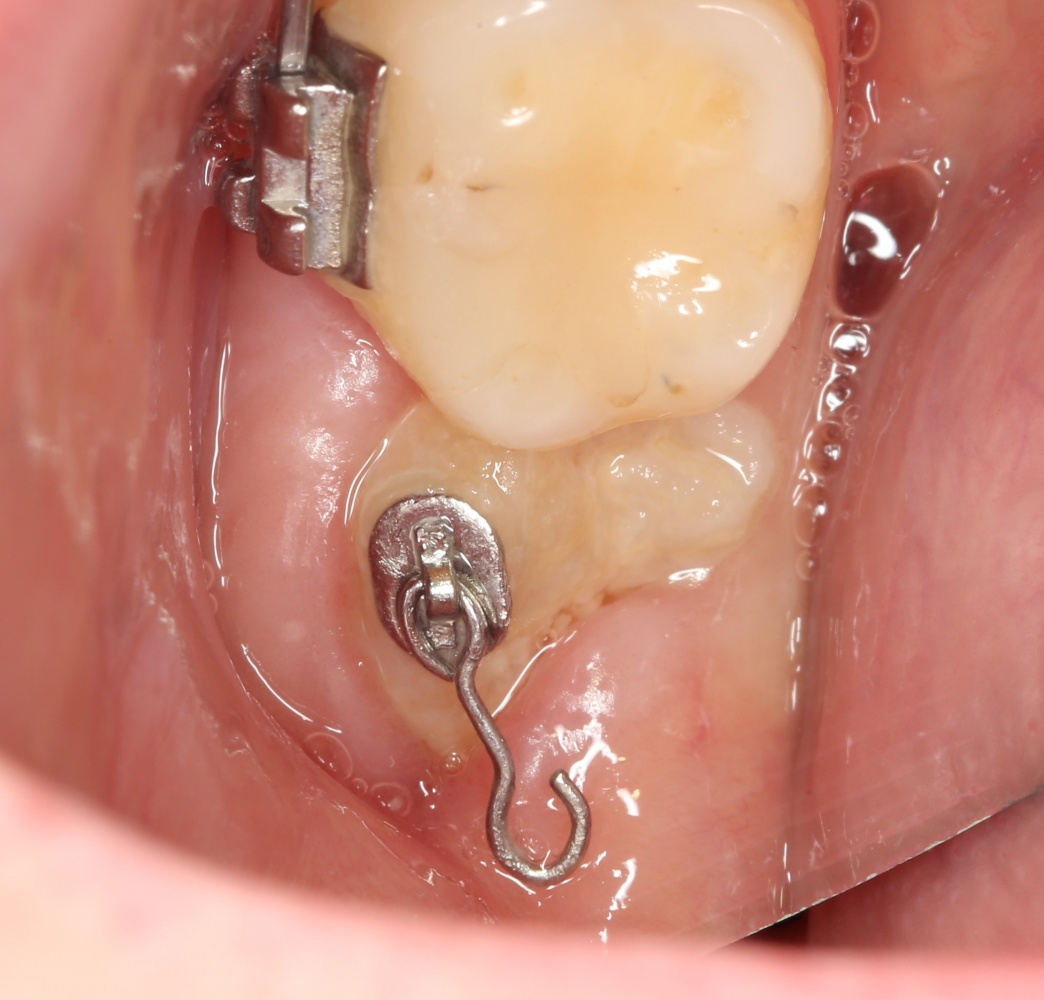

Через два дня послеоперационная рана выглядит следующим образом:

Как понимаете, пациентку ничто не беспокоит. Ну, разве, что отек немного. Он сойдет через 3-4 дня, и она спокойно продолжит работу со своим врачом-ортодонтом.